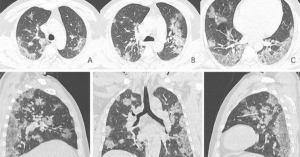

Formation en imagerie COVID

La Société d’imagerie thoracique et la Société Française de Radiologie mettent à disposition régulièrement des cours de formations à l’usage des radiologues et des manipulateurs au fur et à mesure de l’avancée de nos connaissances de cette nouvelle maladie. Vous trouverez au sein des ces cours des informations sur l’épidémiologie de cette infection, sur la place de l’imagerie mais également les différentes mesures de protection au quotidien.

Consulter les cours en ligne »